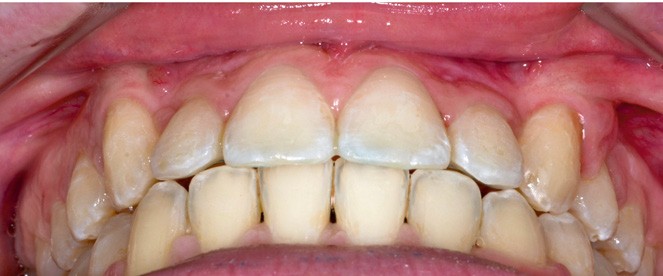

L’appareil est déposé après la mise en place de contentions collées de 12 à 22 et de 33 à 43 avec le port nocturne d’une plaque de Hawley à l’arcade maxillaire. Le temps de traitement actif a été de 41 mois.

Les traitements des transpositions sont souvent complexes car il y a plusieurs facteurs à prendre en compte : la morphologie dentaire, les considérations esthétiques, le stade d’édification radiculaire, la position des couronnes et des racines dans le processus alvéolaire dans les trois plans de l’espace, le temps de traitement et la motivation du patient [1]. L’utilisation d’un renfort d’ancrage transpalatin pour la correction des transpositions de canines est bien documentée dans la littérature [2], d’autant plus que chez ces jeunes patients, idéalement traités avant l’âge de 10 ans [3], la pose d’ancrages osseux en vestibulaire est contre-indiquée au vu de la présence de germes au niveau des sites d’insertions. Le choix d’un dispositif à mémoire de forme, préactivé pour délivrer des forces légères et continues (300-500 g) favorisant l’expansion transversale et la dérotation molaire simultanée sans réactivation manuelle, associé à l’utilisation de bras en TMA reliant les molaires aux canines incluses, nous a permis de profiter du moment généré par la dérotation des 16 et 26 pour emmener les canines en direction vestibulaire. Nous avons ainsi pu préserver les racines des incisives maxillaires lors de la correction des transpositions, de manière simple, contrôlée et confortable pour la patiente, tout en facilitant la phase de multi-attache qui a suivi.